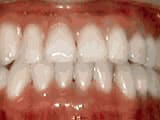

Missing lateral incisors

Before

AfterThis woman’s lateral incisors were missing since birth. She had braces for 20 months to move the teeth into their correct positions, then the missing teeth were replaced with bonded “Maryland” bridges.